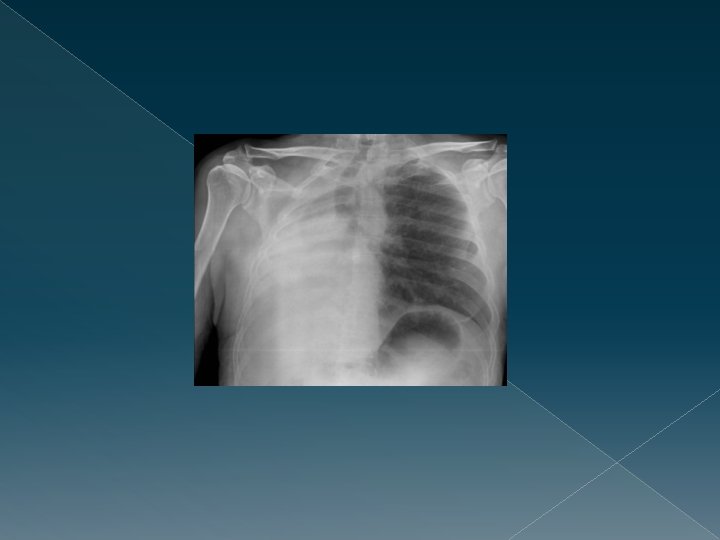

SIGNOS RADIOLÓGICOS DE ATELECTASIA DIRECTOS › Desplazamiento de las cisuras. › Pérdida de aireación, con opacificación del área. Debe acompañarse de otros signos de atelectasia. › Agrupamiento broncovascular. INDIRECTOS › Desplazamiento hiliar hacia la atelectasia › Elevación unilateral del diafragma. › Desviación traqueal. › Desplazamiento cardíaco. En atelectasias muy importantes.

INSUFICIENCIA CARDÍACA Signos radiológicos: CARDIOMEGALIA 2. Redistribución vascular 3. Edema intersticial (lineas B) 4. Derrame pleural 1.